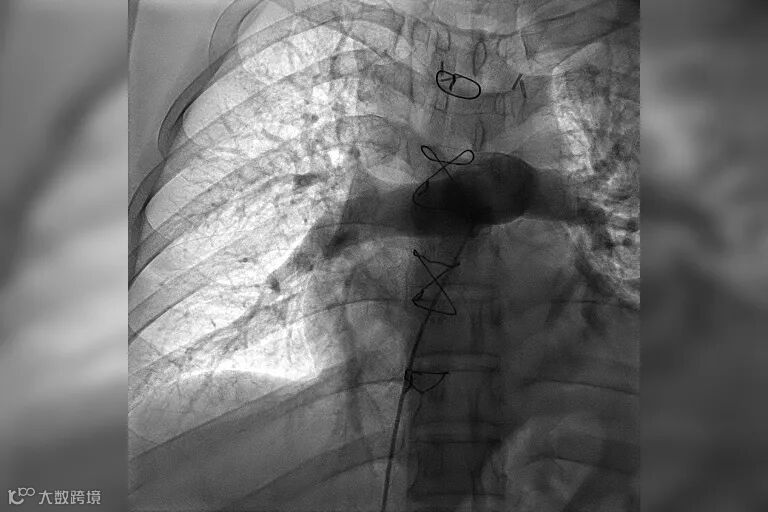

时间就是生命。在我院快速急诊手术准备后,心内科副主任医师王承带着团队进入导管室。只见医生操作娴熟,选用新型取栓支架,灵活地经导管,一条一条地取出大量暗红色血栓。小章即刻感觉呼吸通畅,氧饱和度上升至95%以上。术后复查肺动脉造影术提示他的右肺动脉血栓影已完全消失,肺动脉血流通畅,各项血流动力学指标也明显改善。整台介入手术用时仅用30分钟,就立竿见影地让患者转危为安。

术后复查肺动脉造影术提示肺动脉血流通畅